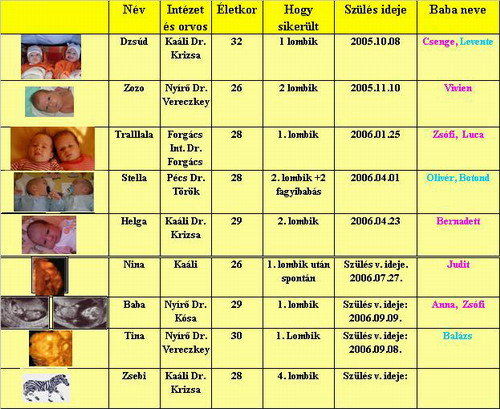

No meg azert szivesen latom a babas kepeket beszamolokat, szoval Helga, Trallala, Baba, Nina (tundi pufok baba lakozik benned is am), Zsebike no meg akiket kihagytam ne hagyjatok ezek nelkul megfoni a panelban